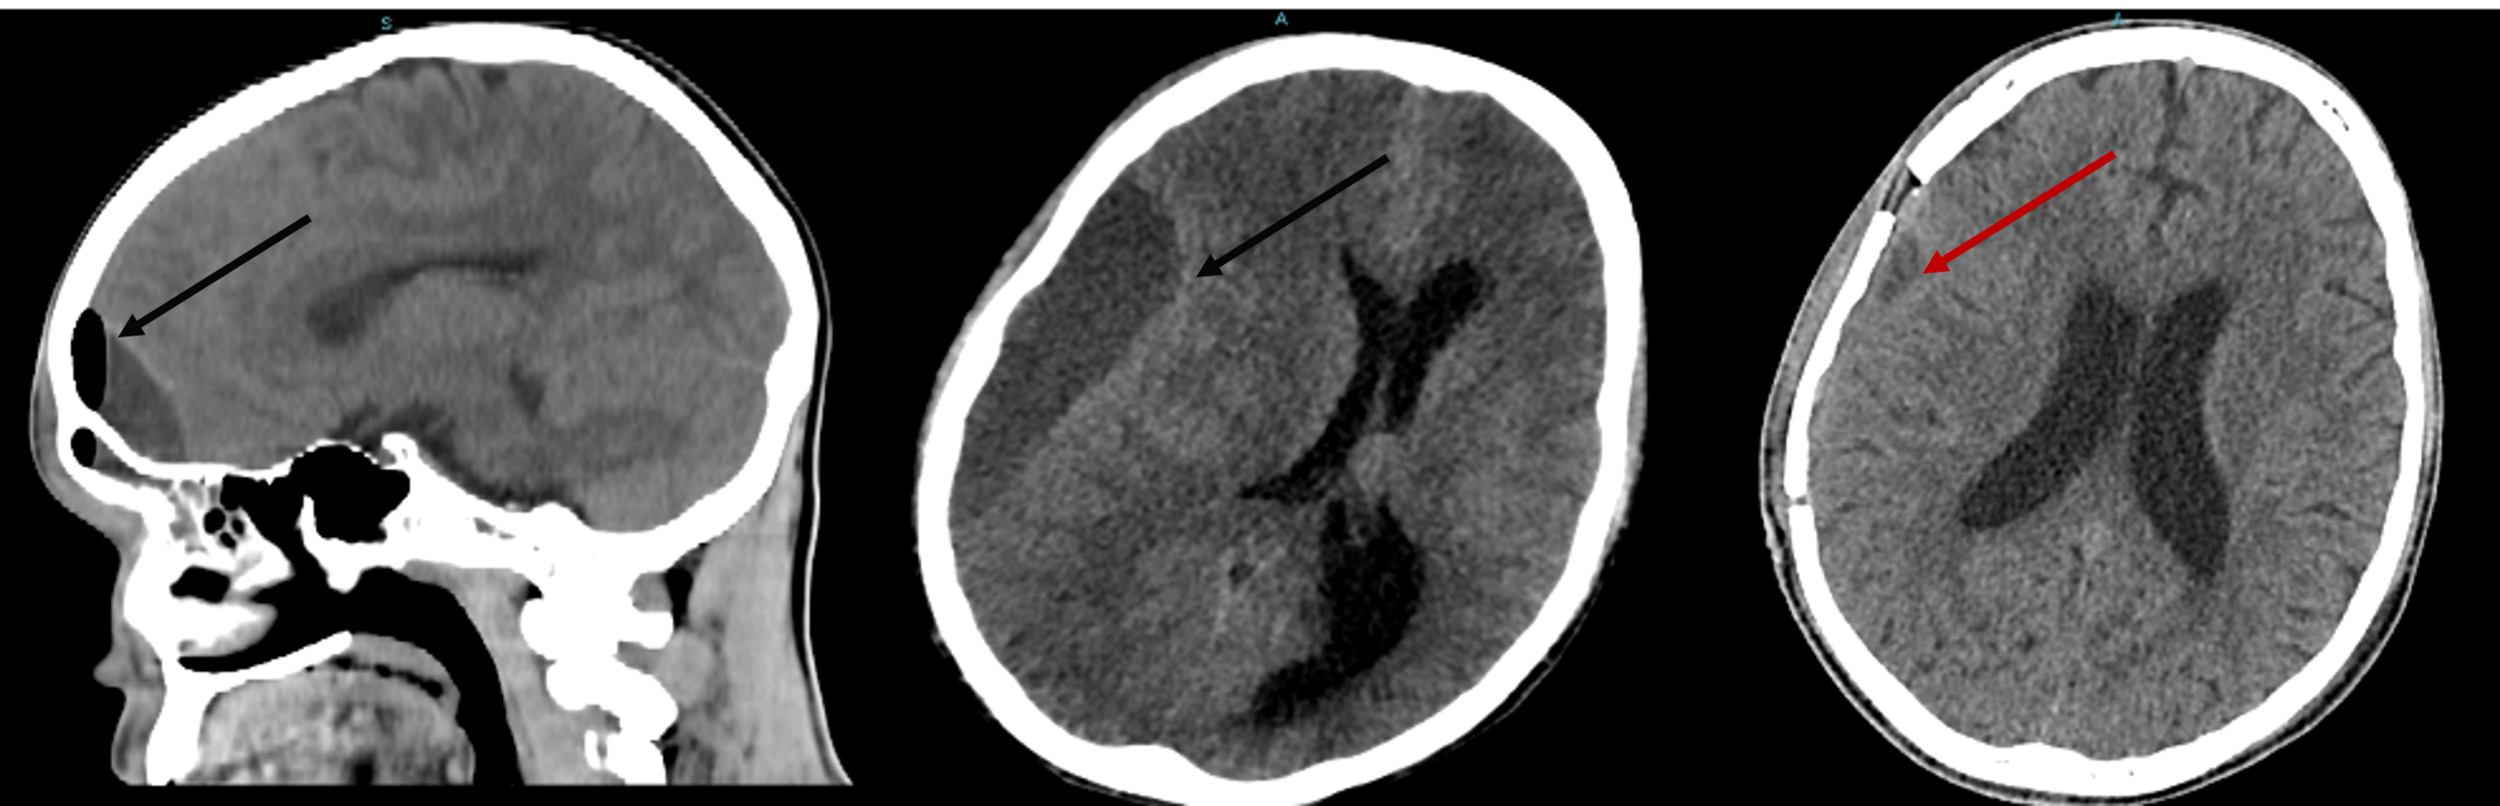

A non-contrast computed tomography scan (CT) of the brain revealed a pansinusopathy and a right frontal collection 12.0 cm3 in size. These findings were suggestive of extradural empyema. Although contrast-enhanced magnetic resonance imaging (MRI) is generally considered superior for diagnosis and surgical planning, MRI was not performed in this case due to limited availability and the urgent need for immediate treatment. The patient underwent urgent surgical drainage of extradural empyema by right supraorbital mini craniotomy. A wound culture obtained during surgery revealed multidrug-resistant Streptococcus constellatus; the antibiotic regimen was subsequently changed to cefepime and vancomycin. On day 15, the patient developed decreased consciousness with a GCS of 6, prompting a CT brain that revealed a right-sided subdural empyema requiring surgical drainage. The procedure was uneventful, and a follow-up CT performed 10 days later showed progressive clinical and neurological improvement during hospitalization. (Figure 1).